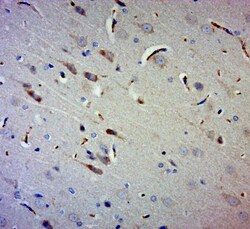

Supportive validation

- Submitted by

- Invitrogen Antibodies (provider)

- Main image

- Experimental details

- Paraformaldehyde-fixed, paraffin embedded rat brain; Antigen retrieval by boiling in sodium citrate buffer (pH6.0) for 15min; Block endogenous peroxidase by 3% hydrogen peroxide for 20 minutes; Blocking buffer (normal goat serum) at 37°C for 30min; Antibody incubation with Gigaxonin Polyclonal Antibody, Unconjugated (bs-11025R) at 1:400 overnight at 4°C, followed by a conjugated secondary for 20 minutes and DAB staining.